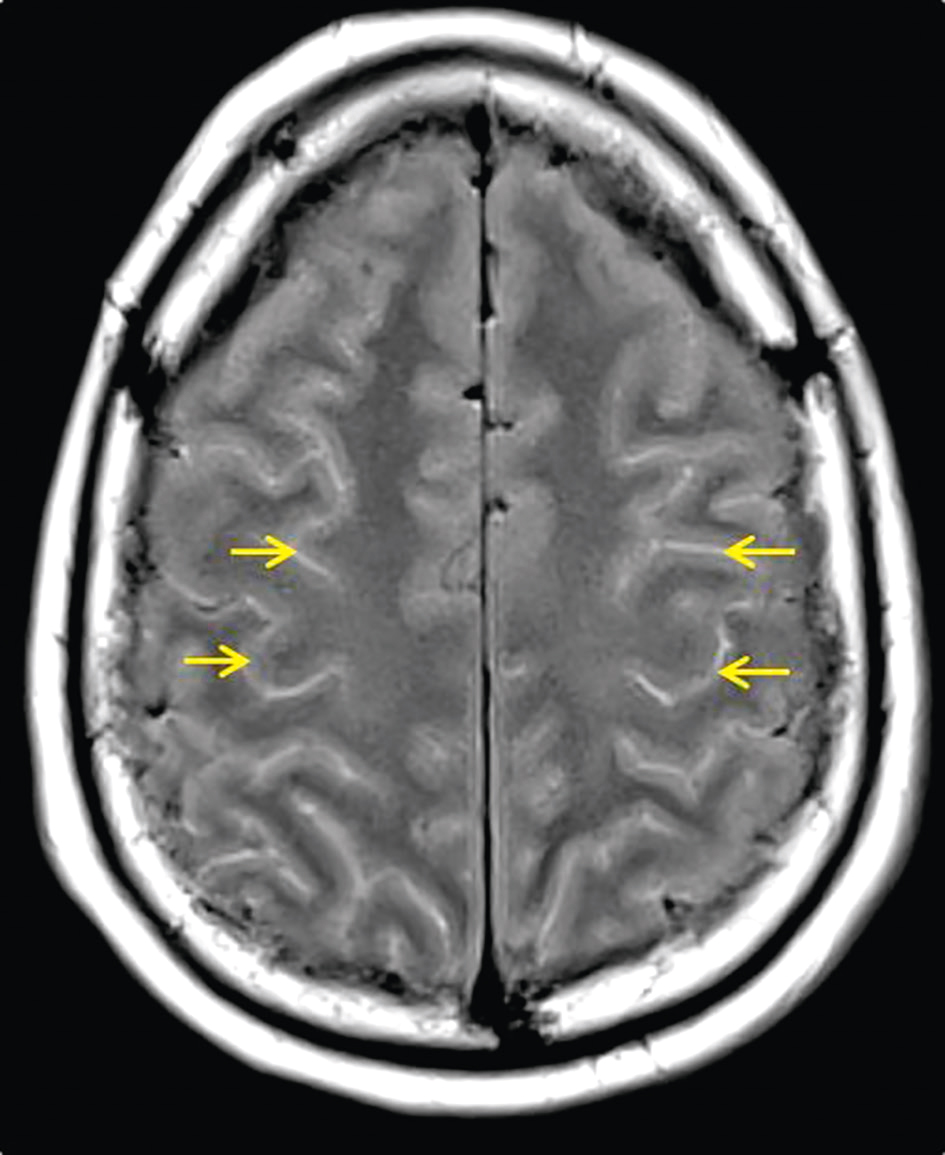

• • soit à visée étiologique en cas de signes encéphalitiques : dans ce cas, l’IRM cérébrale sans et avec injection de gadolinium doit être privilégiée du fait de sa meilleure sensibilité. Elle peut montrer des lésions parenchymateuses en hypersignal T2 et T2-FLAIR, touchant volontiers les régions temporales et frontales, avec prise de contraste. Une méningite peut être visible sous forme d’hypersignaux diffus en séquences FLAIR au sein des sillons corticaux (fig. 24.2) avec prise de contraste des leptoméninges en séquence T1 gadolinium. D’autres lésions peuvent être retrouvées en fonction du micro-organisme en cause. Néanmoins, une IRM normale n’élimine pas le diagnostic d’encéphalite ou de méningite. À défaut d’IRM, un scanner cérébral sans et avec injection de produit de contraste iodé doit être pratiqué;

Les hypersignaux des sillons corticaux sur l'IRM en séquence FLAIR suggèrent une inflammation liée à une méningite à pneumocoque, essentielle pour le diagnostic et le suivi.

Fig. 24.2 Figure IRM cérébrale en séquence FLAIR montrant des hypersignaux diffus des sillons corticaux (flèches) chez un patient présentant une méningite à pneumocoque.

L'IRM cérébrale en séquence FLAIR montre des hypersignaux diffus des sillons corticaux chez un patient présentant une méningite à pneumocoque. La séquence FLAIR est utilisée pour détecter des anomalies dans le cerveau en supprimant le signal du liquide céphalorachidien, ce qui permet de mieux visualiser les lésions. Les hypersignaux diffus des sillons corticaux, indiqués par des flèches, sont des zones où le signal est anormalement élevé, suggérant une inflammation ou une infection. Dans ce cas, ces hypersignaux sont caractéristiques de la méningite à pneumocoque, une infection bactérienne grave des méninges, les membranes qui entourent le cerveau et la moelle épinière. L'inflammation causée par l'infection entraîne une accumulation de liquide et de cellules inflammatoires dans les sillons corticaux, rendant ces zones visibles sur l'IRM. Ces images sont essentielles pour le diagnostic et le suivi de la méningite à pneumocoque, car elles permettent de visualiser l'étendue de l'inflammation et d'évaluer la réponse au traitement. En résumé, les hypersignaux diffus visibles sur l'IRM en séquence FLAIR indiquent une inflammation due à une méningite à pneumocoque, fournissant des informations cruciales pour le diagnostic et la gestion de cette condition chez le patient.